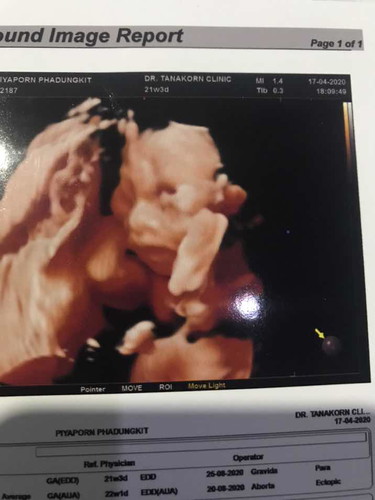

บ้านไหนตั้งครรภ์ 5เดือน น้องน้ำหนักตัวเท่าไหร่กันแล้วคะ. บ้านนี้หาหมอมาวันนี้ ลุงหมอบอกว่าน้อง500กรัมแล้ว

บ้านนี้ตอน5เดือนน้องหนัก589gจ้า